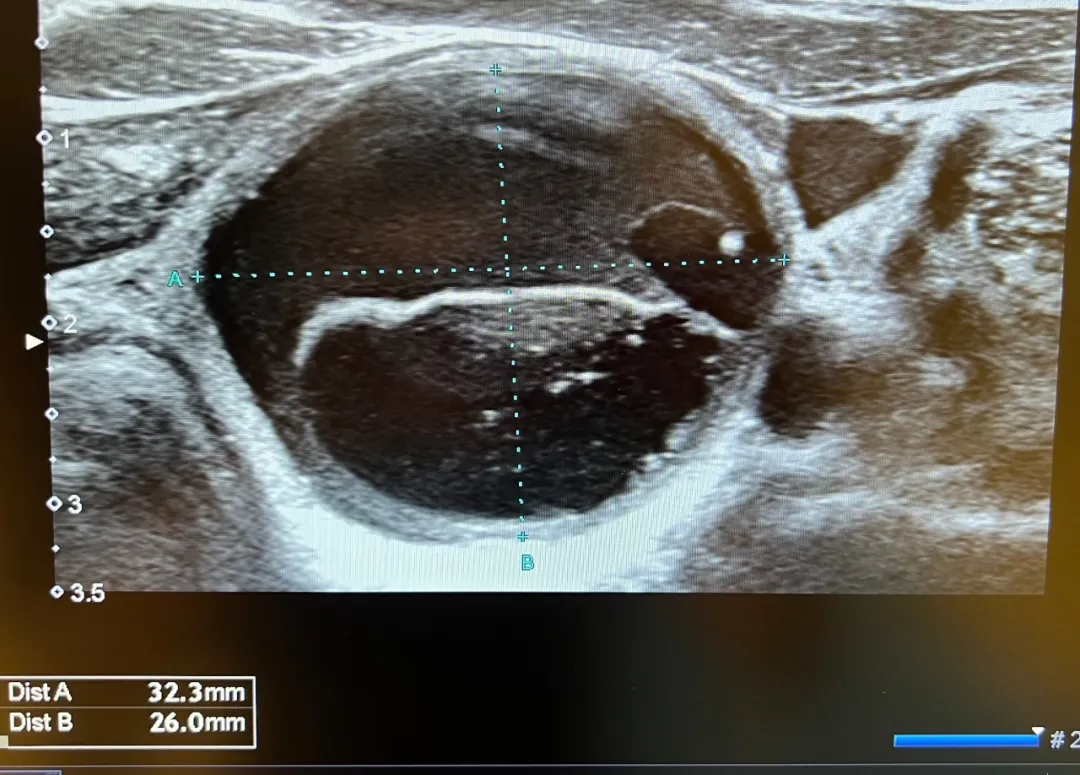

內(nèi)容提要 2025年7月4日,葫蘆島市第二人民醫(yī)院超聲科王云霞主任團隊完成遼西首例超聲引導下甲狀腺囊腫聚桂醇硬化治療術(shù),53歲的趙女士(化名)成為首位受益者——僅通過一個1毫米針眼,便解除了困擾多年的3.2厘米囊腫。這項以“精準、微創(chuàng)、高效”為核心的技術(shù),標志著遼西甲狀腺疾病微創(chuàng)治療進入新階段! PART.01 病例回顧 囊腫增大壓迫生活,微創(chuàng)治療成首選 趙女士數(shù)年前體檢發(fā)現(xiàn)甲狀腺結(jié)節(jié),近期復查其甲狀腺右葉囊腫已增大至3.2×2.6cm,導致頸部腫脹、呼吸吞咽異物感等壓迫癥狀,嚴重影響生活質(zhì)量。傳統(tǒng)開放手術(shù)雖能切除囊腫,但存在創(chuàng)傷大、恢復慢及頸部留疤等問題,而王云霞團隊采用全新引進的國際領(lǐng)先超聲引導下聚桂醇硬化治療術(shù),僅使用1毫米細針,術(shù)后不留疤痕,趙女士欣然接受了手術(shù)方案。 術(shù)前照片及影像 PART.02 填補空白 毫米級“針功夫”化解囊腫危機 術(shù)中視頻 手術(shù)在局麻下進行,超聲科王云霞、鄧兆姝主任團隊通過一根直徑僅1mm的細針,精準避開甲狀腺血管和神經(jīng),穿刺至囊腫內(nèi)部,抽盡囊內(nèi)液體,緩解囊腫對周圍組織的壓迫;注入聚桂醇硬化劑反復沖洗囊壁,破壞內(nèi)皮細胞,誘發(fā)無菌性炎癥反應(yīng);保留部分聚桂醇溶液。整個過程僅耗時30分鐘。術(shù)后趙女士頸部只留一個針眼,無任何并發(fā)癥,當日即可恢復正常生活。 術(shù)后照片及影像 PART.03 技術(shù)特色 聚桂醇硬化治療優(yōu)勢 此項技術(shù)填補了遼西甲狀腺囊腫硬化治療的空白,對于甲狀腺囊腫、乳腺囊腫、腎囊腫、肝囊腫以及卵巢囊腫等不愿接受手術(shù)切除的患者,其“精準可視、微創(chuàng)無疤、療效顯著、恢復快”的綜合價值為患者提供了理想替代方案: ?精準可視:超聲實時引導,全程可視化、安全避開血管神經(jīng)、無輻射; ?微創(chuàng)無疤:無需開刀,針眼僅1mm,美觀無痕; ?療效顯著:治愈率高達95%以上,并發(fā)癥少; ?恢復快:全程無痛,當天即可恢復正常生活,隨治隨走。 葫蘆島市第二人民醫(yī)院持續(xù)深化甲狀腺疾病診治中心建設(shè),創(chuàng)新開設(shè)甲狀腺超聲專家門診,為患者提供精準化超聲檢查、專業(yè)化病情評估及微創(chuàng)介入治療等一站式診療服務(wù),實現(xiàn)“檢查-診斷-治療”全流程閉環(huán)管理,以優(yōu)質(zhì)醫(yī)療服務(wù)守護濱城百姓甲狀腺健康。 PART.04 人民醫(yī)院 人民名醫(yī) 王云霞 副主任醫(yī)師 ·葫蘆島市第二人民醫(yī)院超聲科主任 ·中國研究型醫(yī)院學會委員 ·中國研究型醫(yī)院學會沖擊波醫(yī)學專業(yè)委員會超聲學組委員 ·中國中國醫(yī)學裝備協(xié)會超聲分會委員 ·遼寧省超聲醫(yī)學工程學會理事會理事 ·遼寧省醫(yī)師協(xié)會超聲分會委員會委員 ·遼寧省中西醫(yī)結(jié)合委員會超聲分會委員 ·葫蘆島市醫(yī)學會超聲委員會副主委 專業(yè)特色:擅長甲狀腺、乳腺、肌骨、神經(jīng)、腹部(婦科)三維超聲和產(chǎn)前篩查、心臟、血管漏后評估等疑難病的超聲診斷;特別是超聲引導下甲狀腺(乳腺)結(jié)節(jié)、前列腺腫瘤、周圍型肺癌及淋巴結(jié)轉(zhuǎn)移癌的穿刺活檢等介入超聲診療;甲狀腺囊腫固化治療、甲狀腺結(jié)節(jié)消融治療及甲乳腫瘤術(shù)后的超聲評估。 鄧兆姝 副主任醫(yī)師 ·葫蘆島市第二人民醫(yī)院超聲科副主任 ·中國研究型醫(yī)院學會肌骨及淺表超聲科專業(yè)委員會青年委員 ·遼寧省醫(yī)學會超聲醫(yī)學分會委員 專業(yè)特色:甲狀腺、乳腺疾病超聲精準診斷;超聲引導下穿刺活檢(細針/粗針);全身臟器超聲造影;甲狀腺囊腫硬化治療;甲狀腺癌術(shù)后超聲隨訪評估;甲狀腺結(jié)節(jié)微波/射頻消融治療。開展甲狀腺結(jié)節(jié)多模態(tài)超聲評估(彈性成像+造影)、乳腺BI-RADS分類精準診斷、消融治療全程超聲監(jiān)控等特色技術(shù),以“精準診斷+微創(chuàng)治療”為臨床特色。 PART.05 甲狀腺疾病診治中心 葫蘆島市第二人民醫(yī)院甲狀腺疾病診治中心,整合并發(fā)揮院內(nèi)多個學科資源優(yōu)勢,聯(lián)合甲狀腺外科、甲狀腺內(nèi)科、核醫(yī)學科、超聲科建立MDT多學科聯(lián)合診療模式,為患者提供“一站式診療服務(wù)”。 甲狀腺疾病的治療手段齊全、技術(shù)領(lǐng)先,開展甲狀腺的外科治療、內(nèi)科治療、同位素碘治療、中醫(yī)中藥治療。中心將邀請國內(nèi)著名甲狀腺外科、內(nèi)科、超聲科、核醫(yī)學科專家定期出診、查房、會診、手術(shù)治療,從甲狀腺疾病的早期發(fā)現(xiàn)、早期治療、長期用藥管理到慢病申報和隨訪,實現(xiàn)甲狀腺疾病全程管理。 診療范圍 01 ? 甲狀腺形態(tài)改變:甲狀腺良性結(jié)節(jié)、甲狀腺惡性結(jié)節(jié)、甲狀腺高功能腺病。 ? 甲狀腺功能改變:甲狀腺功能亢進、甲狀腺功能減退、妊娠甲狀腺疾病、甲狀腺炎、甲狀腺相關(guān)性眼病、亞急性甲狀腺炎、甲狀腺慢病管理。 ? 其他疾?。捍贵w前葉功能減退、低T3綜合癥、垂體TSH腺瘤。 ? 甲狀腺旁腺疾病。 中心優(yōu)勢 02 ? 著名專家云集:中心引入國內(nèi)知名三甲醫(yī)院甲狀腺領(lǐng)域著名專家,包括學科帶頭人、博士生導師、國務(wù)院政府特殊津貼專家等,致力于甲狀腺疑難病診療。 ? 微創(chuàng)手術(shù)技術(shù)成熟:每年開展甲狀腺和甲狀旁腺手術(shù)500余例,尤其精通復雜病例處理,如甲狀腺癌根治、腺瘤切除、結(jié)節(jié)性甲狀腺腫次全切等,技術(shù)實力領(lǐng)先業(yè)界。 ? 超聲微創(chuàng)消融精準消除:開展超聲引導下甲狀腺結(jié)節(jié)細針穿刺、超聲引導下甲狀腺病損微波消融等微創(chuàng)診斷、治療技術(shù),實現(xiàn)甲狀腺結(jié)節(jié)的精準定位與無損消除。 ?高端設(shè)備助力診斷治療:運用PET-CT、SPECT-CT顯像及功能測定等尖端技術(shù),為甲狀腺及甲狀旁腺疾病提供深度檢查與精準診斷,同時,放射性核素療法在甲亢及分化型甲狀腺癌治療中展現(xiàn)顯著療效。